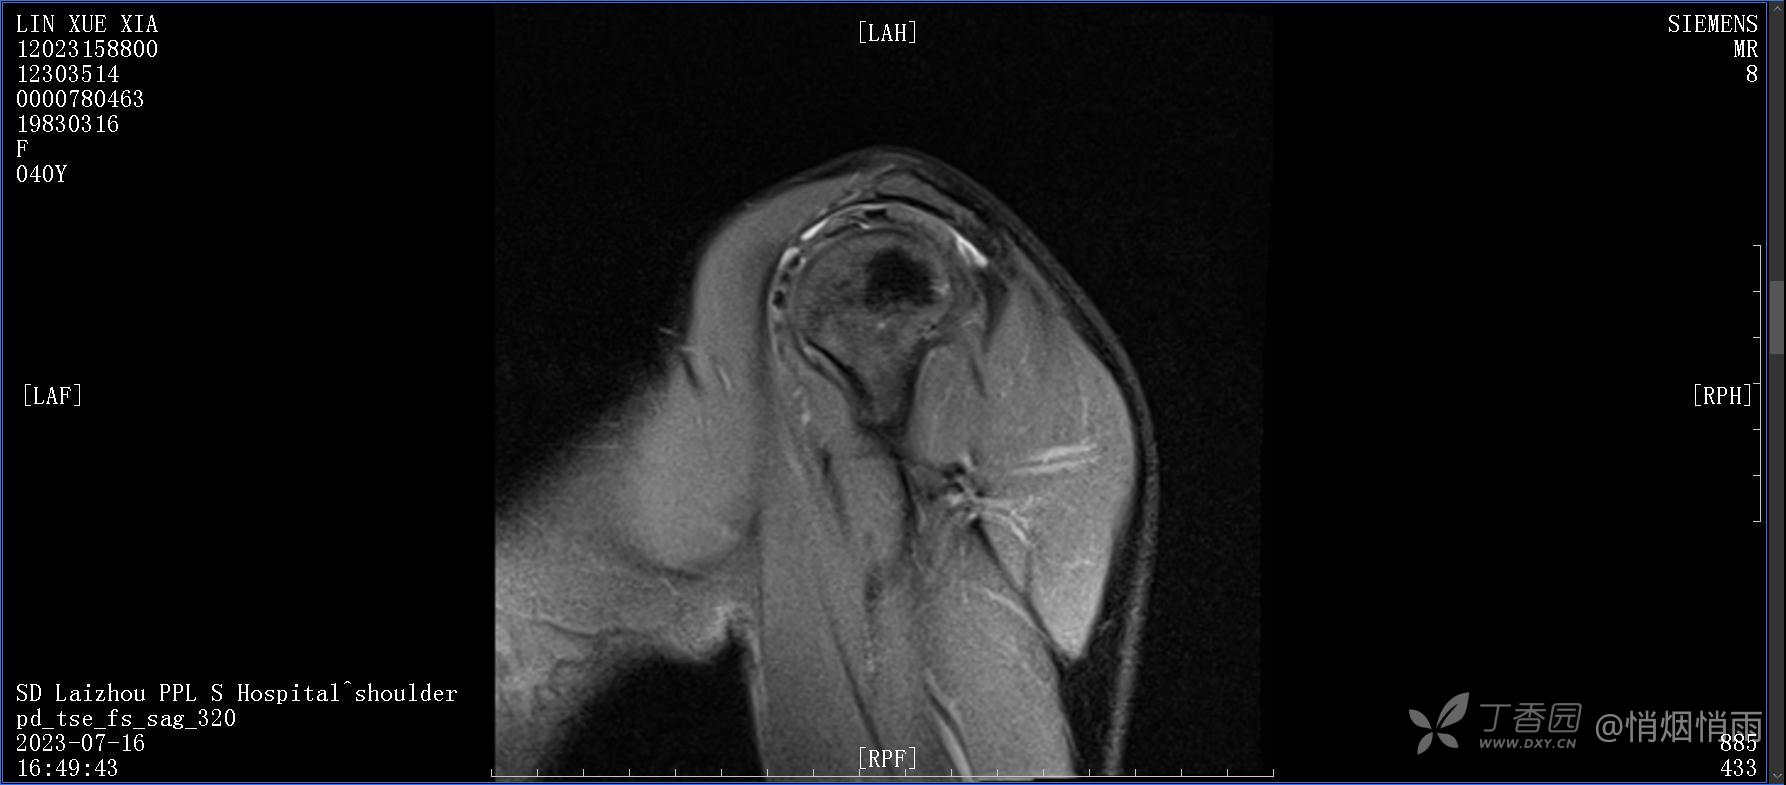

查体:右肩关节局部轻度肿胀,肩胛区压痛明显,痛处不固定,肩关节痛性活动受限,jobe test(+),lift -off test(+),中指、环指感觉较余指减退,余肢端感觉及血运情况可。

目前的诊断,暂时依据辅助检查诊为肩袖损伤,但是患者疼痛的性质和特点,却不是单纯的肩袖损伤所致。考虑过胸廓出口综合征,但是该疾病会出现肩胛区的疼痛吗?(由于考虑到费用的问题,没再进行下一步的检查)带状疱疹会有如此的症状吗?